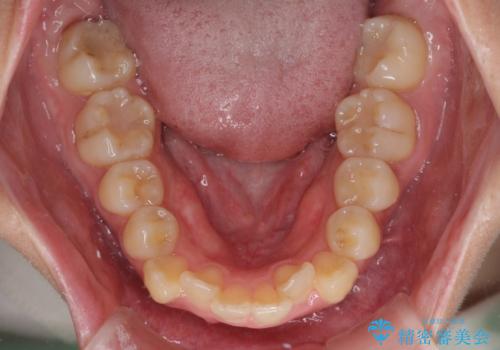

口の閉じにくさが改善され、横顔のシルエットも大幅に改善されました。